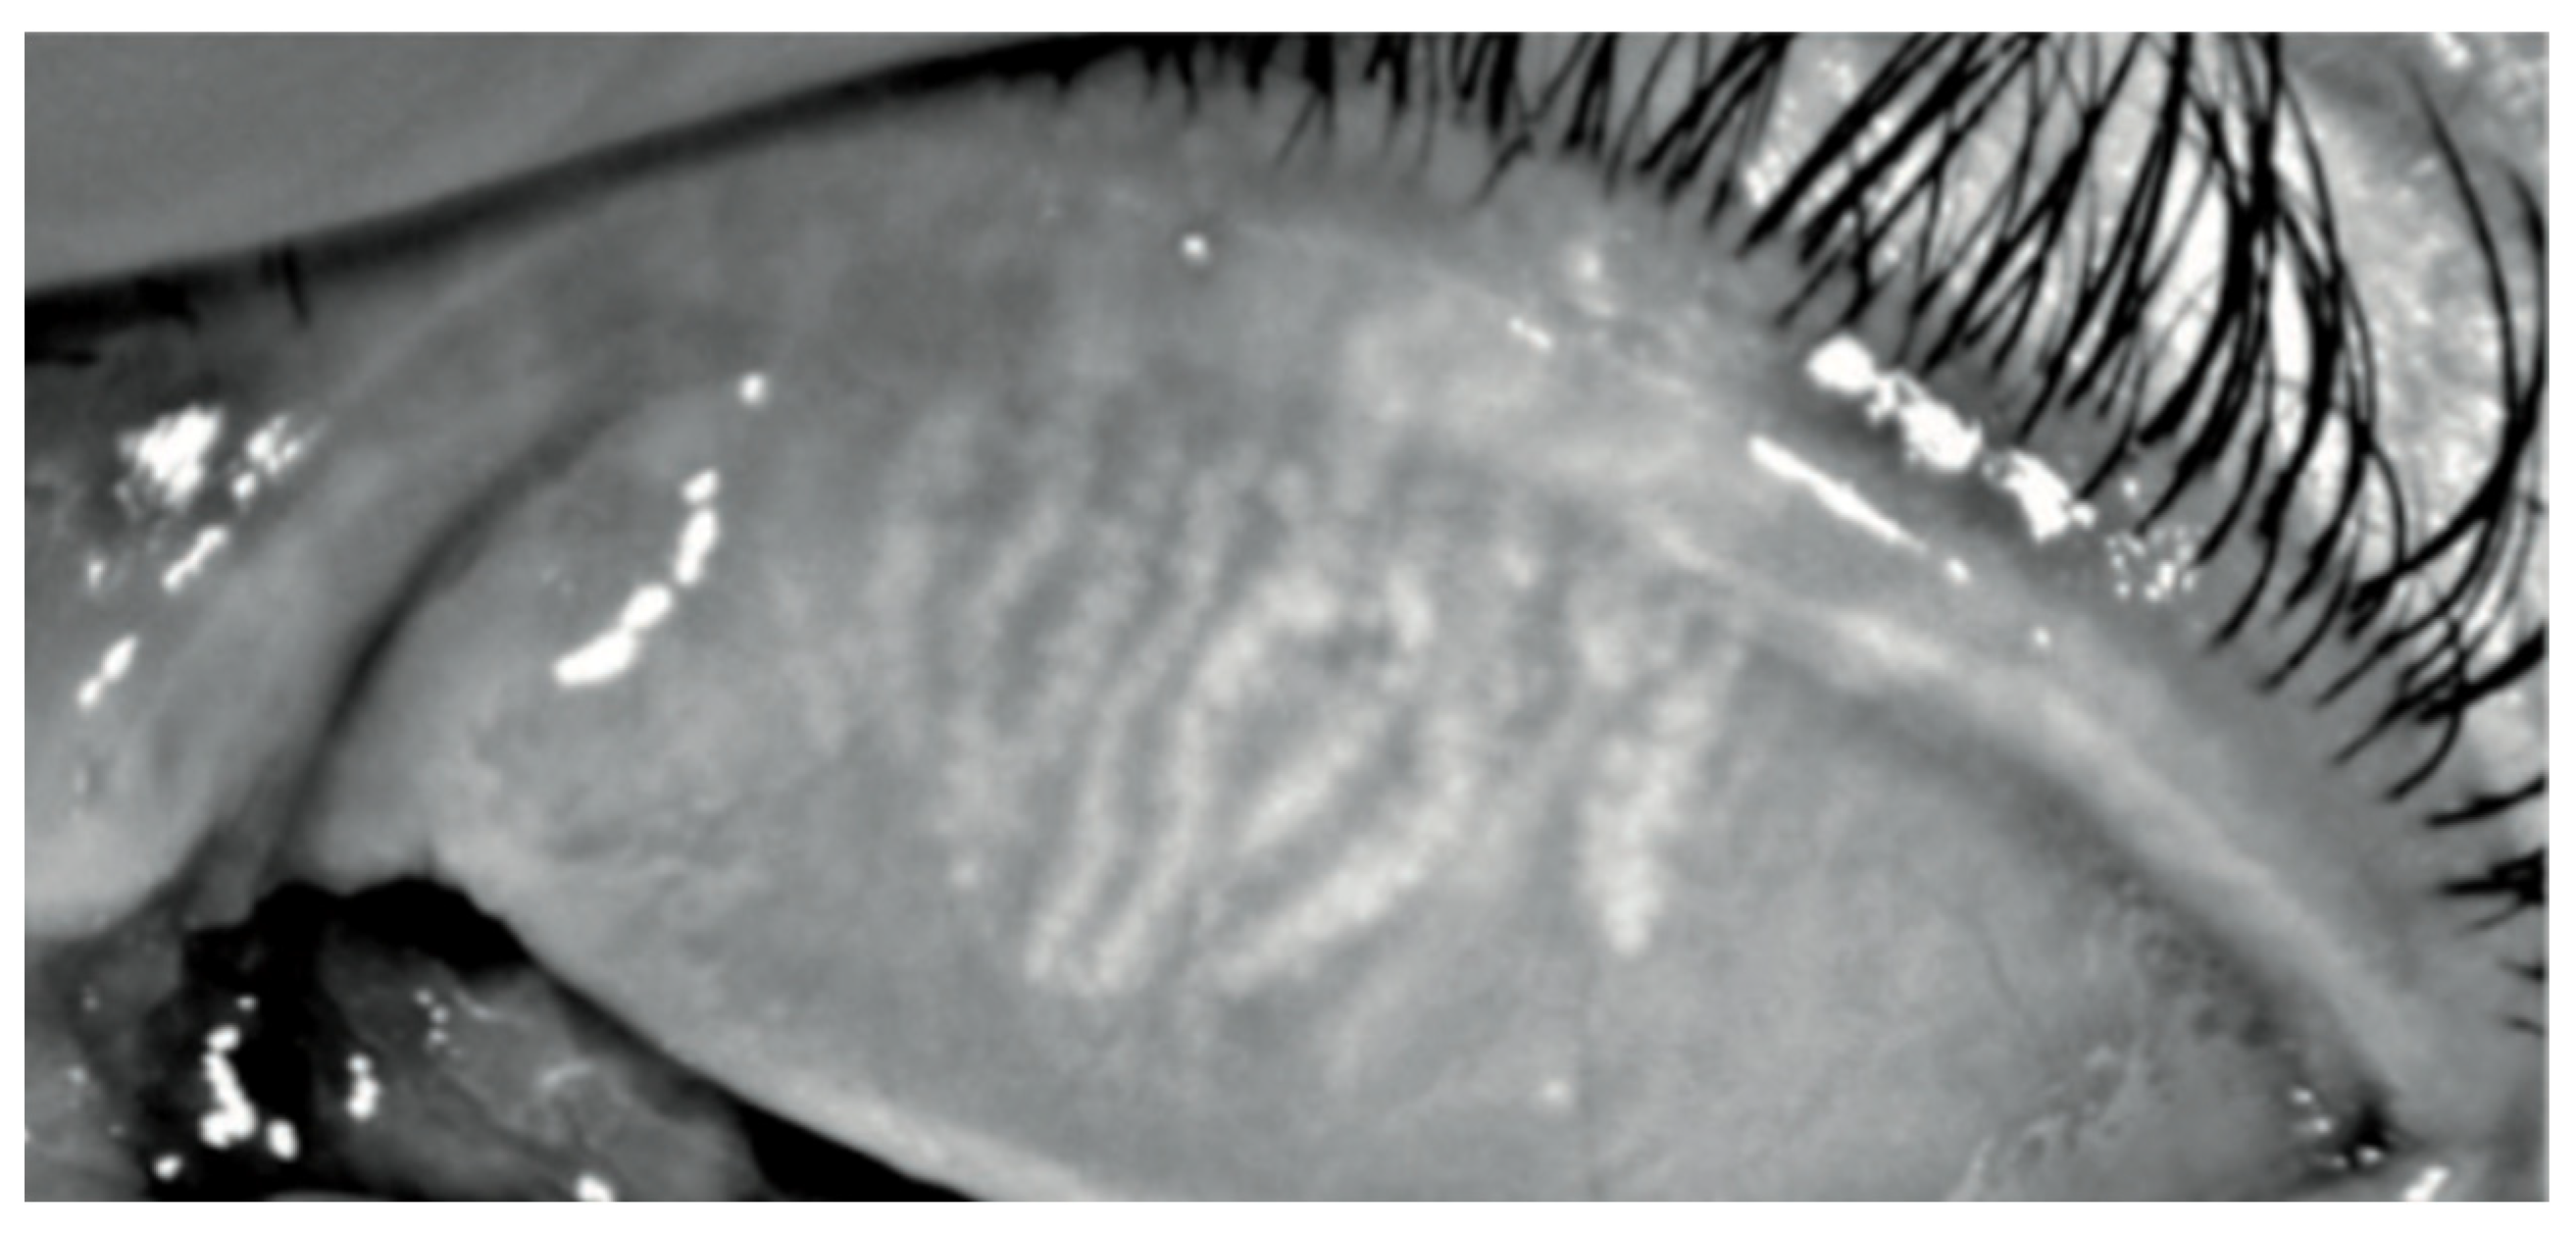

In Group 2, we observed that both eyelids showed mild-to-moderate distorted anatomy at Meibography. At the confocal examination, we observed a decrease in the goblet cell population in the conjunctival epithelium in this group (5.2 cells/mm); in some cases, goblet cells totally disappeared (Figure 5). In tarsal conjunctiva, inflammatory cells were present, and more concentrated around the adenoid lumina of the meibomian glands. We observed several cell infiltrates, composed of a mix of round cells and cells with multilobate nuclei compatible with neutrophils, which were probably a sign of an inflammatory process involving the conjunctiva (Figure 6).

Meibomian glands showed up as hyperreflective, edematous, and with a dilated acinar structure with a blurred lumen contour, that can be referred to as a meibomitis sign.

In vivo confocal microscopy provides non-invasive high-resolution images of ocular surface tissues, bypassing the need for biopsy and/or impression cytology. Our in vivo images of bulbar and tarsal conjunctiva, acquired by confocal microscopy, confirmed the reduction in intraepithelial goblet cells as reported in the literature in patients treated with Dupilumab (Figure 5) [7]. Goblet cells are round cells, that occur mainly individually or in clusters, and normally account for 10% of the conjunctival epithelial cells [17]. We found a mean value of 5.2 cells/mm. In addition, the in vivo images show inflammatory cells in the tarsal conjunctiva and around the adenoid lumina. We assumed that the inflammation could be the cause behind the dropout of glands.

Figure 6. In vivo images of bulbar conjunctiva of a treated patient: several cell infiltrates are present, probably a sign of an inflammatory process involving the conjunctiva.